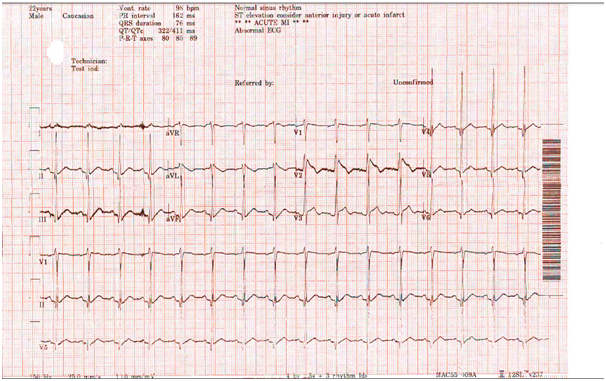

His initial ECG (Figure 1), showed sinus rhythm , RSR pattern in V1 And V2 with ST- elevation in V1 and V2 ECG. We were asked to see the patient as the ECG changes were interpreted as acute myocardial infarction. The ECG was later interpreted by cardiology staff to be typical changed of type 1 brugada syndrome, then asked to do ECG with higher position of v1,v2 (Figure 2) shows more pronounced changes(coved ST elevation) and (Figure 3) demonstrate the effect of normalization of body temperature with complete resolution of the ECG changes. The patient was admitted to cardiology monitored bed started on antipyretic medication as well as antibiotics, later he developed more fever and had recurrence of his ECG changes (Figure 4). He was counselled regarding the need for electrophysiological study, genetic counselling and need for defibrillator.

Figure 1 Initial ECG.